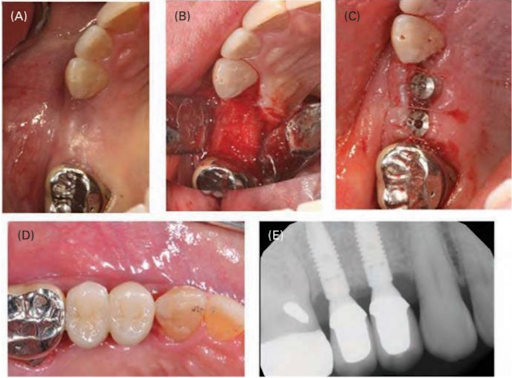

Thực hiện GBR sau khi lật vạt toàn bộ (A), khoan xương vỏ của xương bên dưới (B), tiếp theo là đặt màng (C) và xương ghép hạt đồng loại (D). Vạt được kéo lại và khâu để đóng kín vị trí phẫu thuật (E, F). Rạch giữa mào xương tại vị trí #15 và #14, mở rộng sang răng kế cận giống như đường rạch khe nướu. Khoan xương vỏ của xương bên dưới bằng mũi khoan tròn nhỏ để tế bào từ xương dễ dàng đi vào vùng ghép trong quá trình lành thương. Xương ghép hạt đồng loại được hòa tan bão hòa trong nước cất khử ion rồi cho vào thiếu hồng. Màng được lèn vào bên dưới vạt phía ngoài và phía trong để che phủ toàn bộ xương ghép hạt.

Tách màng xương ở vạt phía ngoài để tăng thêm sự di động cho phần vạt phía trên nhằm đạt được sự đóng kín ban đầu (hoàn toàn) mà không bị căng. Kích thước của màng được quyết định dựa trên kích thước của thiếu hồng và được cắt tỉa tương ứng. Màng phải lớn hơn thiếu hồng ít nhất 3 mm. Xương ghép hạt đồng loại được hòa tan bão hòa trong nước cất khử ion rồi cho vào thiếu hồng. Màng được lèn vào bên dưới vạt phía ngoài và phía trong để che phủ toàn bộ xương ghép hạt.

Vạt được định vị và khâu bằng chỉ không tiêu. Đầu tiên sử dụng mũi khâu đệm ngang để kéo mép vạt, sau đó sử dụng mũi khâu rời để đóng kín ban đầu. Sau 2 tuần, cắt chỉ và lau vùng này bằng chlorhexidine. Các răng kế cận được làm sạch nhẹ nhàng bằng dụng cụ cạo vôi tay. Sau 4 tháng lành thương, xương phía ngoài đã tăng lên đáng kể, và 2 implant (đường kính 3.5 mm x chiều cao 11mm) được đặt (theo hướng dẫn của nhà sản xuất) mà không cần phải ghép thêm. Hai tháng sau cấy ghép, tiến hành làm phục hình trên implant.

(A) Bốn tháng sau phẫu thuật GBR. (B) Đủ xương chiều ngang tại thời điểm đặt implant. Implant được đặt (C) và làm phục hình (D). (E) Phim quanh chóp của implant đã làm phục hình. Sau 4 tháng lành thương, xương phía ngoài đã tăng lên đáng kể, và 2 implant (đường kính 3.5 mm x chiều cao 11mm) được đặt (theo hướng dẫn của nhà sản xuất) mà không cần phải ghép thêm. Hai tháng sau cấy ghép, tiến hành làm phục hình trên implant.